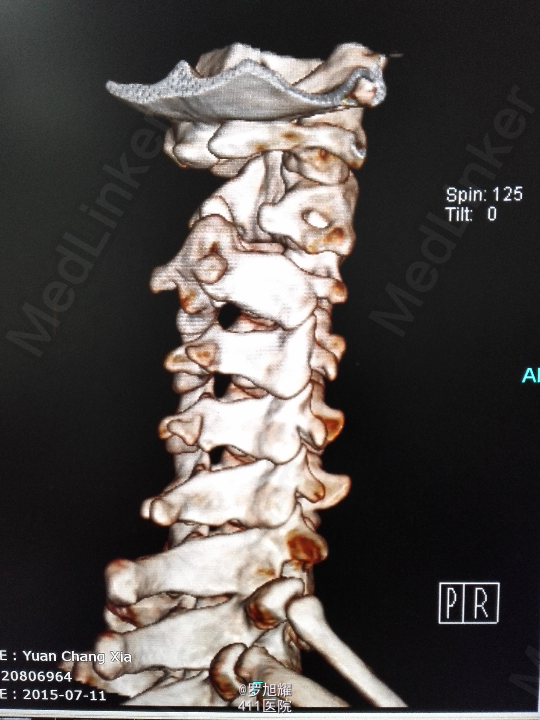

右侧躯体麻木1年,右上肢及下肢麻木2月余。 查体:颈椎活动受限,右上肢肘关节以远痛温觉减退,右侧胸4平面以下痛温觉及触觉减退,四肢肌力尚可,右侧霍夫曼征阳性,右侧上下肢所有腱反射亢进。 颈椎X线示:颈2椎板棘突缺如,颈3棘突肥大增高。 颈椎CT示:颈2椎板棘突缺如,颈3棘突肥大增高,颈2/3椎间盘突出,左侧颈2残留部分椎板进入椎管。枢椎齿突增生,寰枢关节退变。 颈椎MRI示:颈2/3椎间盘突出,左侧颈2椎板进入椎管,颈髓受压变性。

查体:颈椎活动受限,右上肢肘关节以远痛温觉减退,右侧胸4平面以下痛温觉及触觉减退,四肢肌力尚可,右侧霍夫曼征阳性,右侧上下肢所有腱反射亢进。 颈椎X线示:颈2椎板棘突缺如,颈3棘突肥大增高。 颈椎CT示:颈2椎板棘突缺如,颈3棘突肥大增高,颈2/3椎间盘突出,左侧颈2残留部分椎板进入椎管。枢椎齿突增生,寰枢关节退变。 颈椎MRI示:颈2/3椎间盘突出,左侧颈2椎板进入椎管,颈髓受压变性。

诊断为:颈椎先天畸形、颈2/3椎间盘突出伴不全瘫。 因寰枢关节退变,颈椎活动已部分受限,而且枢椎椎板棘突缺如,稳定性差,决定后路减压枕颈融合。

因寰枢关节退变,颈椎活动已部分受限,而且枢椎椎板棘突缺如,稳定性差,枕颈融合虽然造成颈部活动受限,但是稳定性好,避免脊髓再次损伤。本例手术后半月上肢麻木明显改善,躯干和下肢麻木尚待恢复。